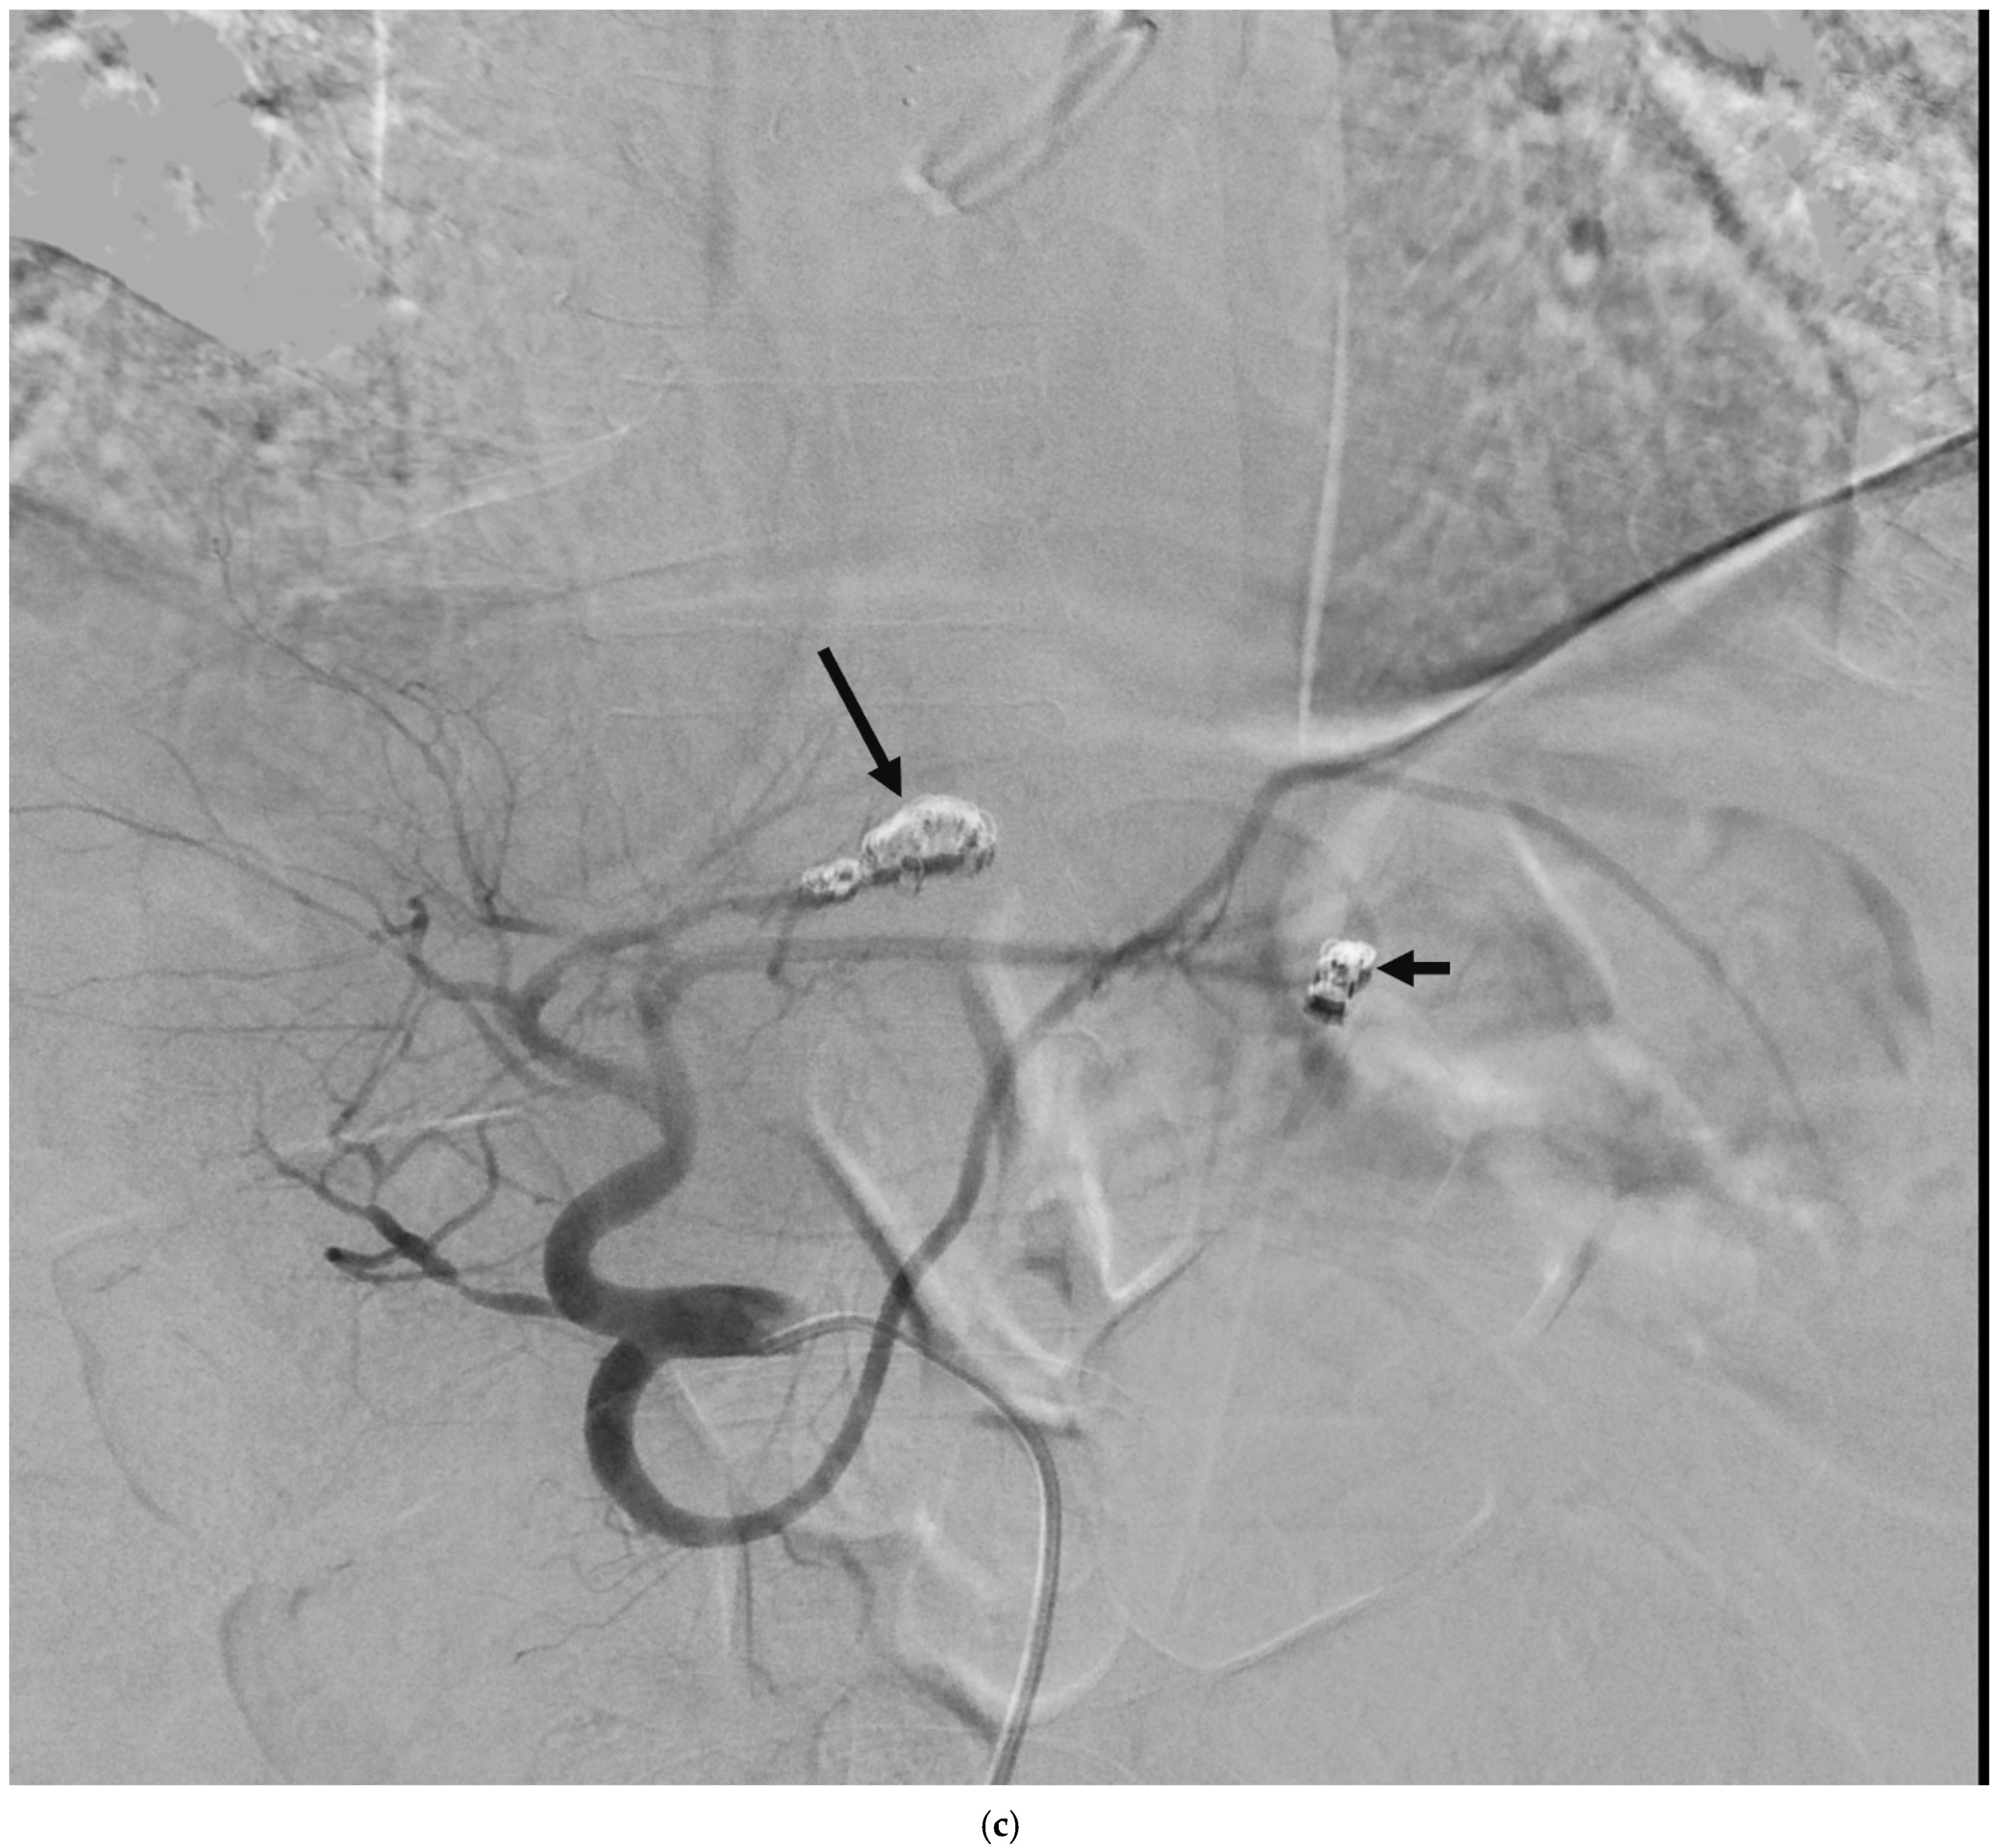

4. Clinical Characteristics of VIAs-Patients